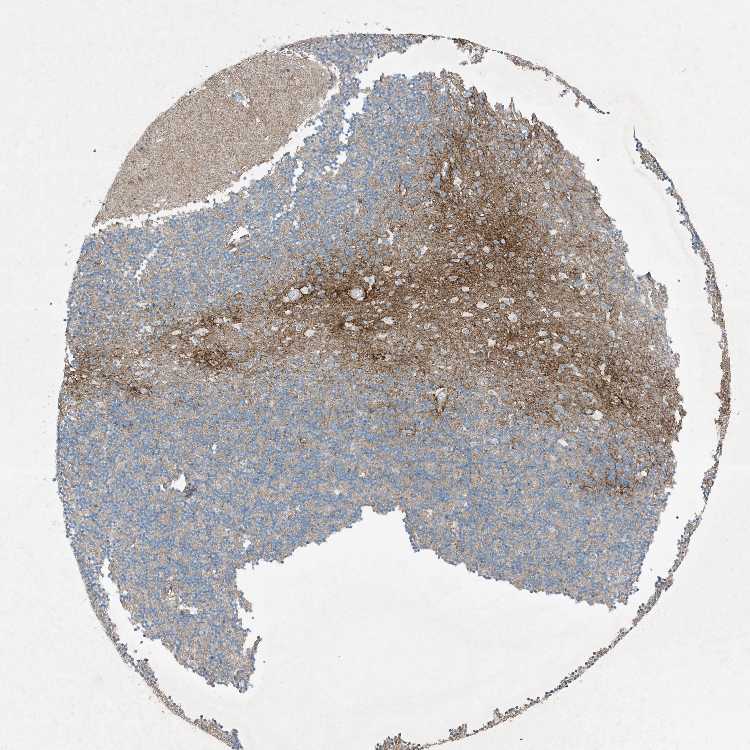

CEREBELLUM - Antibody stainingi

Antibody staining in the annotated cell types in the current human tissue is reported as not detected, low, medium, or high, based on conventional immunohistochemistry profiling in selected tissues. This score is based on the combination of the staining intensity and fraction of stained cells.

Each image is clickable and will lead to virtual microscopy that enables deeper exploration of all samples and also displays staining intensity scores, fraction scores and subcellular localization as well as patient and tissue information for each sample.

Antibody HPA046074Antibody CAB033822

Purkinje cells Not detectedNot detected

Cells in granular layer Not detectedNot detected

Cells in molecular layer Not detectedNot detected